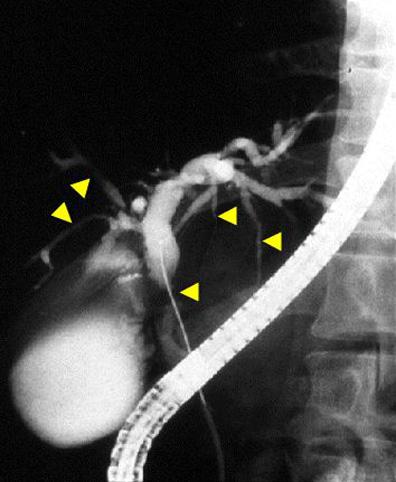

疾病(病理主体)的分类炎症性・溃疡性疾患/溃疡性大肠炎

检查方法X线